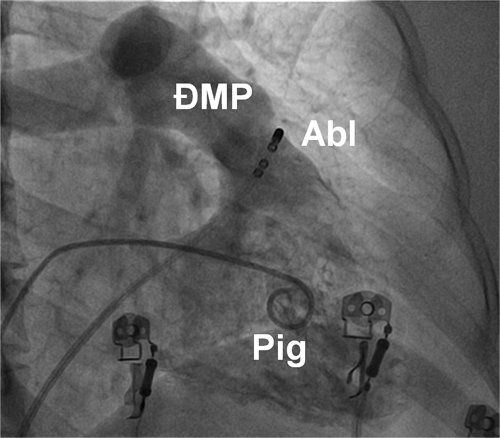

Triệt đốt các cơn tim nhanh thất được thực hiện bằng cách đưa ống thông đốt vào trong các buồng thất qua đường tĩnh mạch hoặc động mạch đùi hoặc qua đường xuyên vách liên nhĩ. Ổ ngoại vị được xác định bằng vị trí ghi được điện thế hoạt hoá nội mạc sớm nhất (earliest activation mapping) hoặc bằng phương pháp tạo nhịp (pace mapping).

Hình 14: Vị trí các ống thông trên hình ảnh X quang trong triệt đốt ngoại tâm thu thất khởi phát từ đường ra thất phải trên góc nghiêng phải 30 độ: Pig: ống thông Pigtail chụp buồng thất phải, Abl: điện cực triệt đốt được đưa vào vùng đường ra thất phải, ngay dưới van động mạch phổi